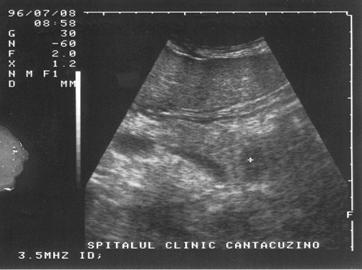

UMBRA ACUSTICA (CONUL DE UMBRA)

Este expresia unei atenuari si a unei reflectari maximale si apare in toate situatiile in care fasciculul de ultrasunete intalneste o structura foarte densa cum ar fi osul sau calculii. Distal de acesta nu mai exista ultrasunete, aspectul final fiind acela al unei "non imagini"; lipsa de ecouri se prezinta ca o structura liniara, de culoare neagra, denumita "con de umbra posterior".

Figura 18. Con de umbra in litiaza renala

Figura 19. Con de umbra posterioara in litiaza biliara